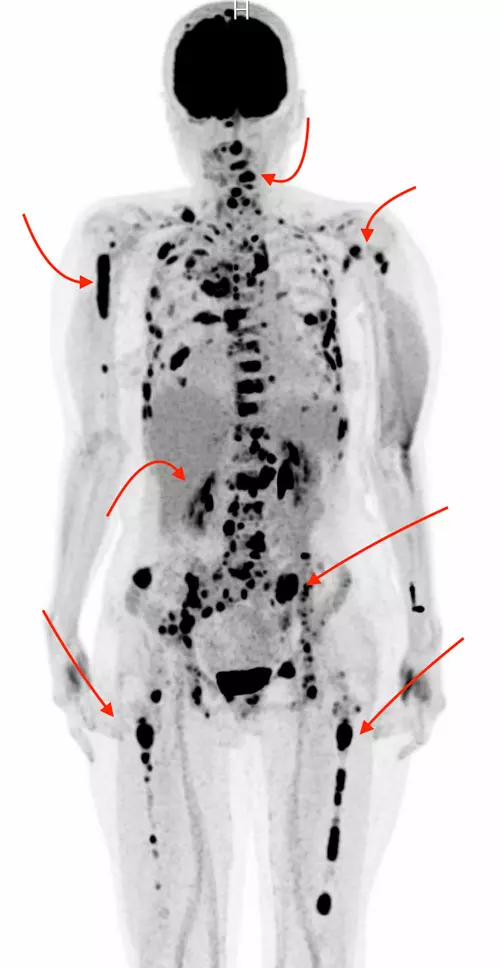

난치성 혈액암인 다발골수종 환자에서, 암이 생기기 전 단계인 ‘전구질환’을 미리 발견하고 추적한 경우가 그렇지 않은 경우보다 생존기간이 더 길다는 사실이 국내 대규모 빅데이터 분석을 통해 처음으로 입증됐다.

분석 결과에 따르면 나이와 동반 질환 등 여러 요인을 보정한 뒤에도, 질환 단계부터 병을 인지하고 선제적 대응을 시작한 환자군이 훨씬 오래 생존하는 것으로 나타났다. MGUS을 거쳐 다발골수종으로 진행된 환자군의 전체 생존기간 중앙값은 약 7.9년, 무증상 다발골수종을 거친 환자군은 약 5.5년이었던 반면, 바로 다발골수종으로 진단된 환자군은 약 4.4년으로, 전구질환 단계에서 먼저 발견된 두 집단이 유의하게 더 오래 생존하는 것으로 나타났다.